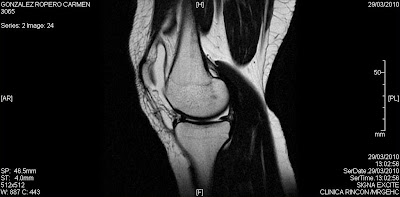

Tras la lesión se hará una comparación de la rodilla lesionada con la otra, para asi descartar derrame. Normalmente este existirá asi que se dificulta la exploración. Hay que esperar a que esta se haya bajado tras varias semanas. Si se aprecia dicha inflamación se hará una radiografía para descartar rotura en huesos, y posteriormente si se ve apropiado una resonancia para ver menisco, ligamentos.. etc

Foto: mi rodilla.